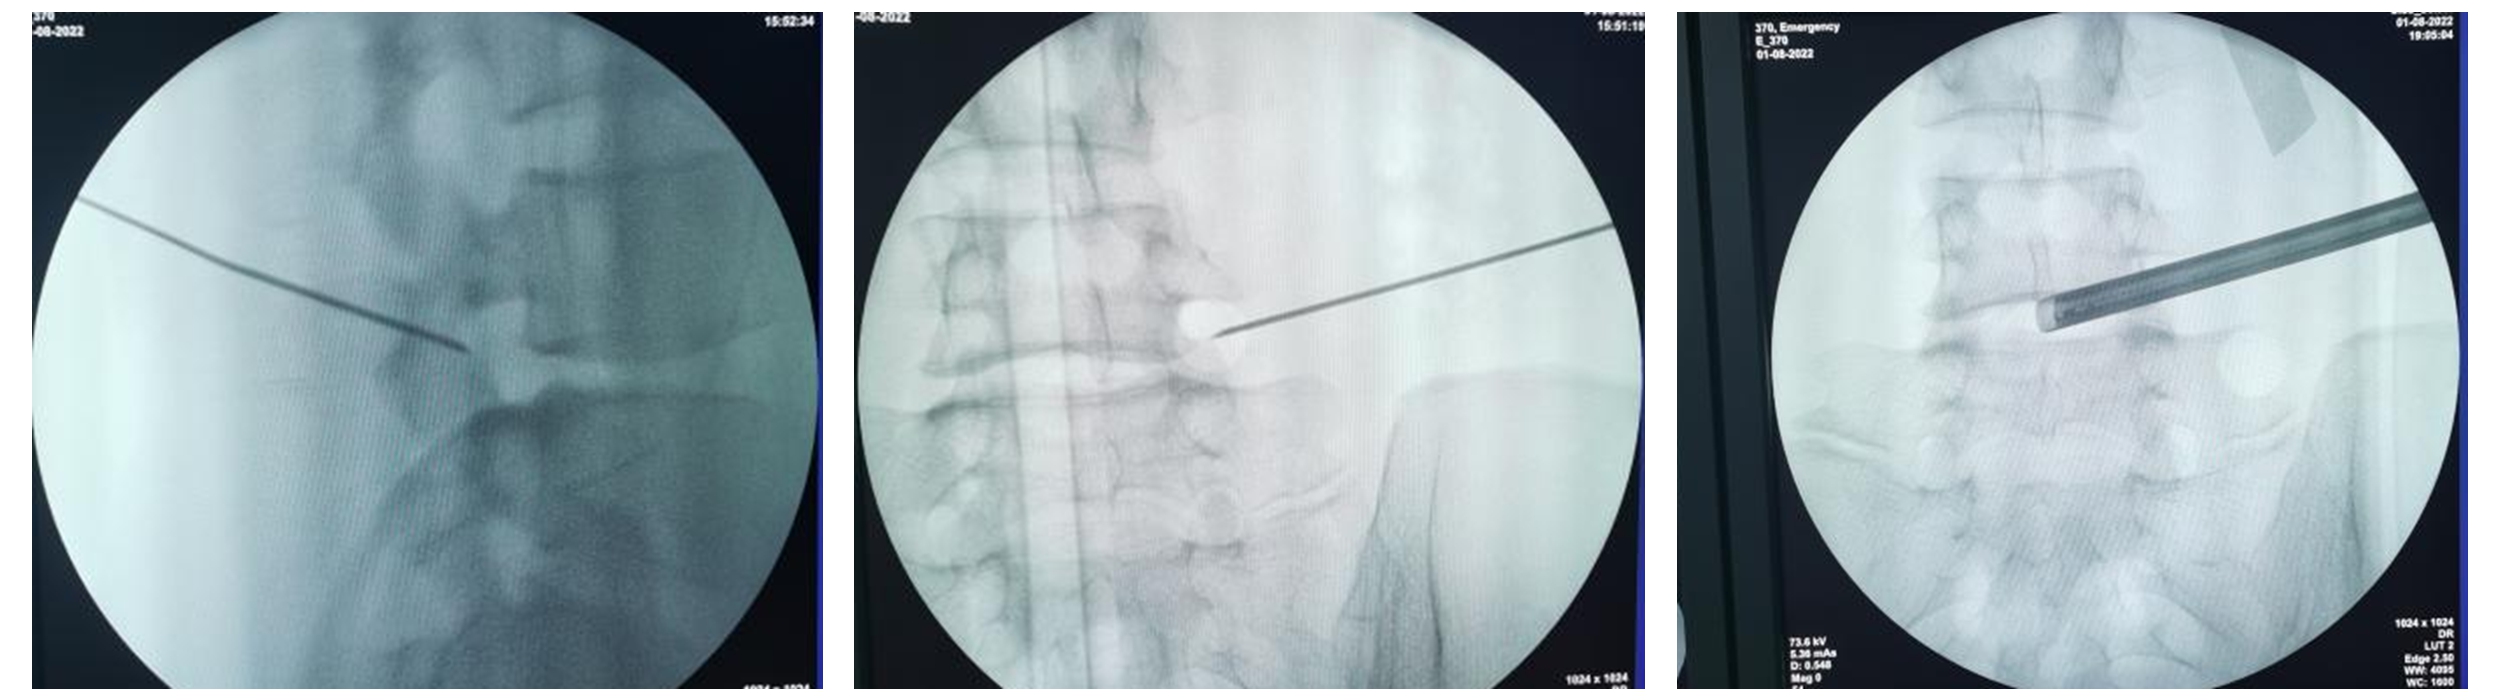

当日,在陈子华主任指导下,脊柱外科微创团队为该患者在实施椎间孔镜下腰4/5椎间盘突出症经椎间孔入路行椎间盘摘除术,手术过程顺利,术中将突出椎间盘组织彻底切除,并将增生骨质在镜下动力磨钻辅助下予以磨除,探查神经根松弛后完全松弛,局麻手术过程中患者全程清醒配合,术后患者自觉下肢麻痛症状即刻改善。